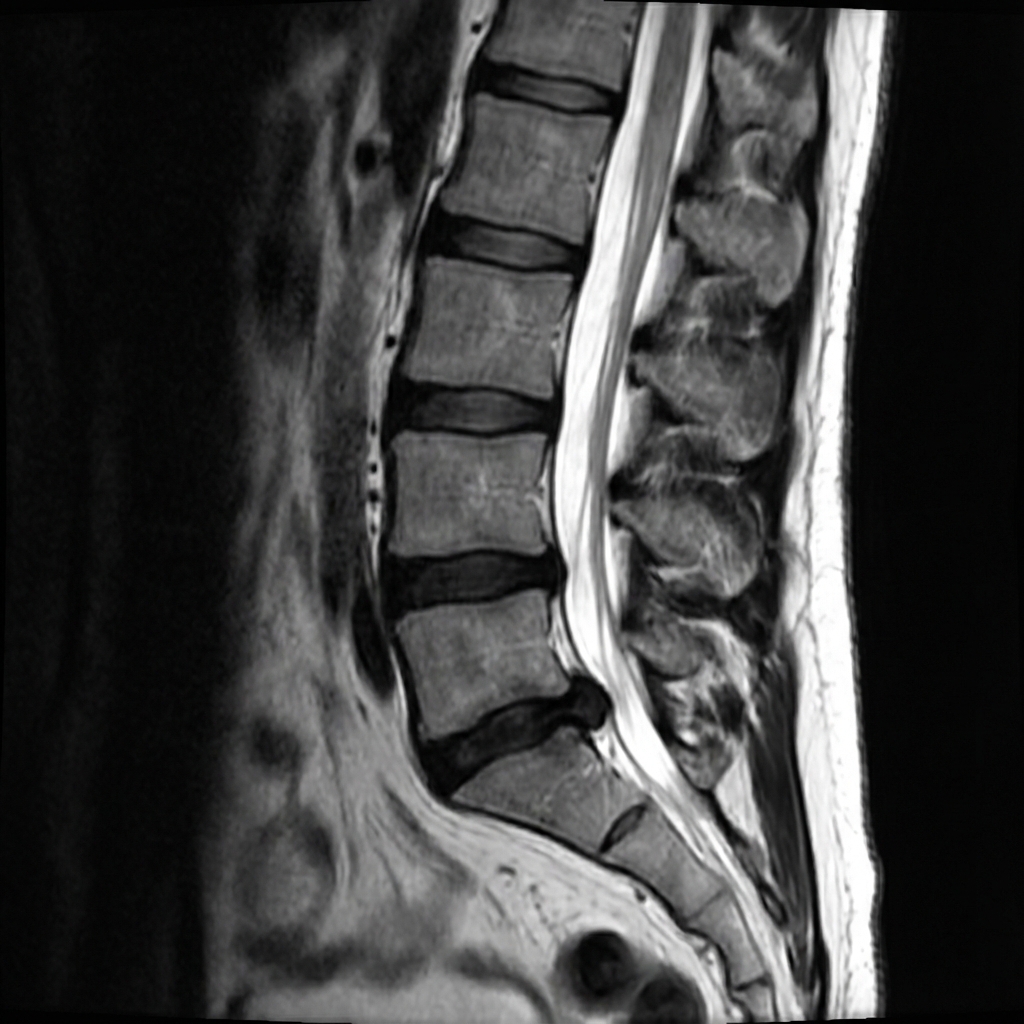

Sagittal and axial T2-weighted MRI demonstrating large left paracentral disc herniation at L5-S1. The disc fragment is extruded and extends inferiorly, compressing the left S1 nerve root in the lateral recess. There is loss of disc height and disc desiccation. The patient has left S1 radiculopathy with calf pain and absent ankle jerk.

Describe the MRI findings and correlate with the clinical presentation.